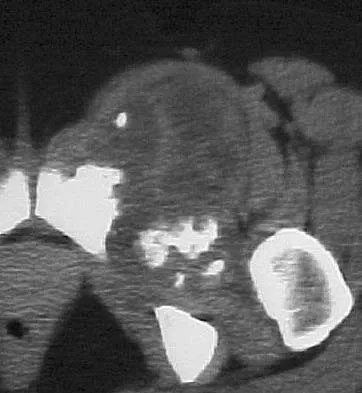

An otherwise healthy 70-year-old man has back and bilateral leg pain in an L5 distribution that is aggravated by standing more than 10 minutes or walking more than 100 feet. He has to sit to get relief. Neurologic and pulse examinations are normal. A radiograph and MRI scan are shown in Figures 4a and 4b. Treatment should consist of

The patient has a degenerative spondylolisthesis at L4-5 with associated spinal stenosis. His symptoms are consistent with neurogenic claudication. Based on these findings, the surgical treatment of choice is decompression and posterolateral fusion. Use of instrumentation is controversial. Laminectomy alone is reserved for the patient who is frail medically. There is no role for an anterior approach or for fusion alone without decompression. Fischgrund JS, Mackay M, Herkowitz HN, et al: Degenerative lumbar spondylolisthesis with spinal stenosis: A prospective, randomized study comparing decompressive laminectomy and arthrodesis with and without spinal instrumentation. Spine 1997;22:2807-2812.